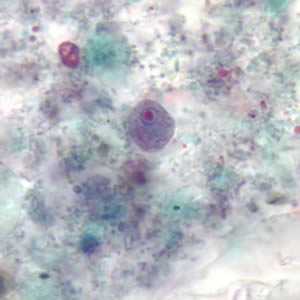

E. hartmanni trophozoites stained with trichrome.

Figure A: Trophozoite of E. hartmanni stained with trichrome. Image courtesy of the Kansas Department of Health and Environment.

Figure B: Trophozoite of E. hartmanni stained with trichrome.

Figure C: Trophozoite of E. hartmanni stained with trichrome. In the upper-right of the image is a cyst-like body of Blastocystis hominis.

Figure D: Trophozoite of E. hartmanni stained with trichrome.

Figure E: Two trophozoites of E. hartmanni stained with trichrome.

Figure F: Trophozoite of E. hartmanni stained with trichrome.